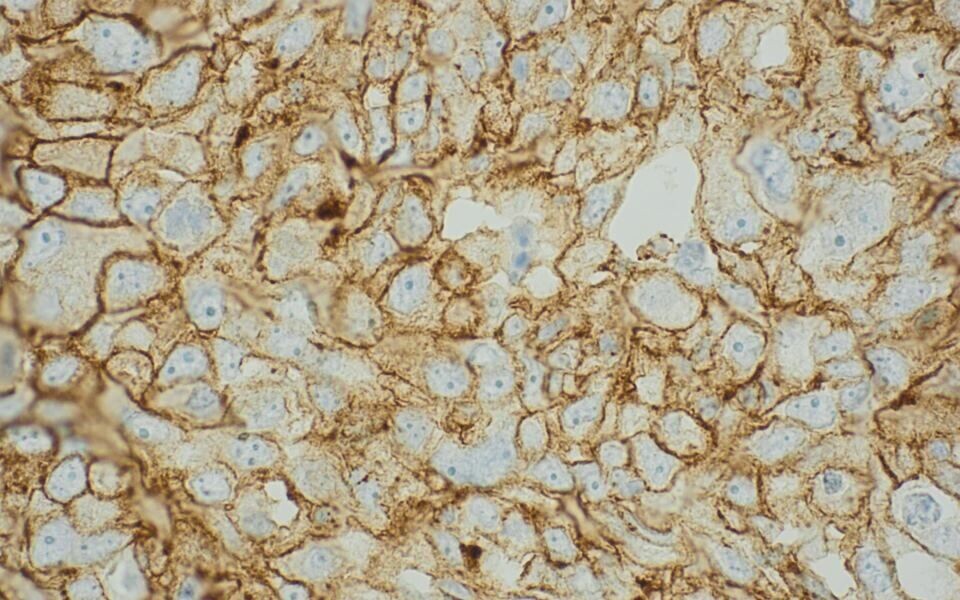

Kreftceller fra pasient som er aktuell for pembrolizumab-behandling. Den brune ringen rundt cellene viser at PD-L1 er til stede. Foto: Universitetssykehuset Nord-Norge

Uttrykk av proteinet PD-L1 i kreftceller er indikasjon for behandling med pembrolizumab. Dette påvises ved hjelp av en immunhistokjemisk analyse. Statens legemiddelverk anslår at cirka 1000 pasienter skal testes per år, og at cirka 700 vil være PD-L1 positive.